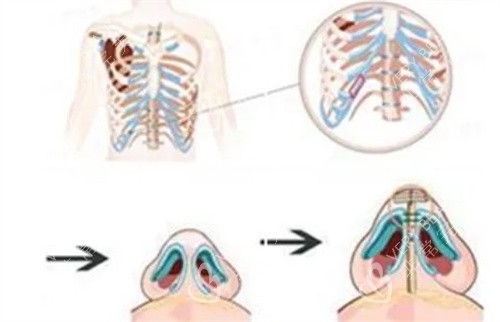

当时,医生跟我介绍说,用自己的肋骨隆鼻,材料取自自身,不会有排异反应,结果也会很自然。我心动不已,毫不犹豫地就做了手术。

我赶紧去医院询问医生,医生告诉我,这是肋骨鼻吸收的正常现象。原来,肋骨在植入鼻子后,会有一定程度的吸收,每个人的吸收情况不同,我的吸收情况相对明显一些。

假体隆鼻使用的是硅胶或者膨体等材料,它们的稳定性比较好,不会像肋骨那样出现吸收的情况。